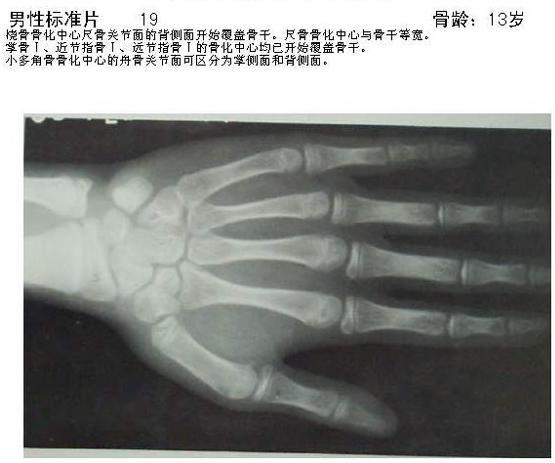

Bkk58.jpg

(555 × 463像素,文件大小:29 KB,MIME类型:

骨龄